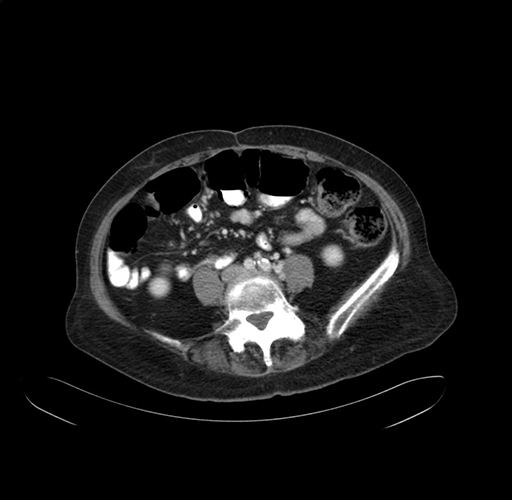

Pre-Chemo: Axial Venous

Axial Venous

Imaging analysis

Based on your CT findings, which issue(s) would give reason for "planned slowing down moment(s)" in this case?

Considering a standard right hepatectomy procedure, what step(s) of the operation would you do differently in this case?